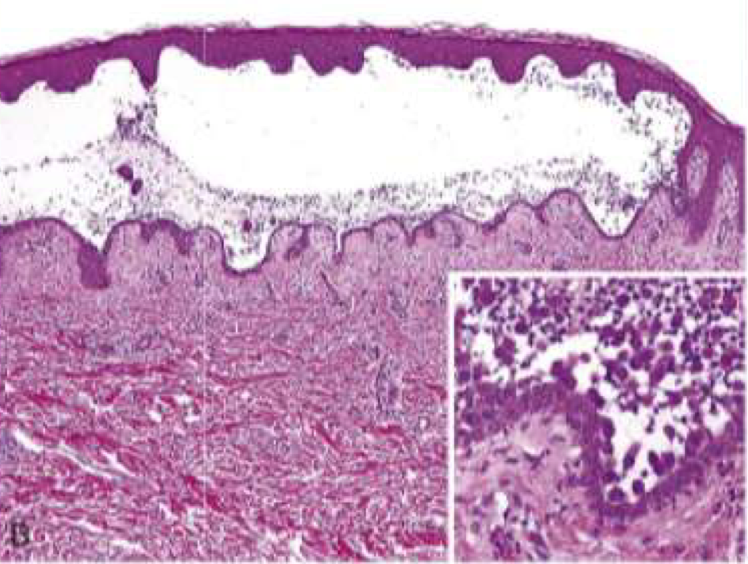

Pemphigus foliaceus blister location

Superficial subcorneal blisters in STRATUM GRANULOSUM (stratum corneum forms roof of bullae)

pemphigus foliaceus